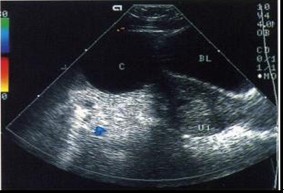

图3黄体囊肿

B超见子宫饱满,宫腔内含胎物(不全流产),子宫上方见一圆形囊肿,壁薄光滑,囊液清亮,张力较大。